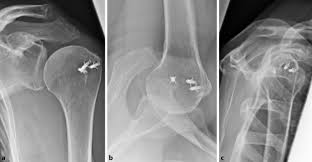

Acromial Spur Relationship To Aging And Morphologic Changes In The Rotator Cuff Journal Of Shoulder And Elbow Surgery

Acromial Spur Relationship To Aging And Morphologic Changes In The Rotator Cuff Journal Of Shoulder And Elbow Surgery from els-jbs-prod-cdn.jbs.elsevierhealth.com

Acromial pseudospur, likely due to inferior slip of deltoid. Acromion morphology and its relationship with sub acromial. Bigliani s types of acromion i,ii,iii 1/3 with ii being around 40%. The morphology of the acromion and its relationship to rotator cuff tears. 3.0% type ii curved (42.9%) angle of anterior. Rehabilitation guidelines for shoulder arthroscopy front view long head of bicep acromion figure 1. The rotator sleeve and acromion will then rub against each other, causing a difficult condition known as impingement. Case contributed by dr sajoscha sorrentino. The acromion process is a bony protuberance extending anteriorly from the superolateral aspect of there are three distinct morphological shapes (bigliani classification) for the undersurface of the. Bigliani, with 618 highly influential citations and 296 scientific research papers. These patients had type ii (curved) acromion, according to bigliani classification. Ebraheim's educational animated video describes the acromion os acromiale.the acromion is a continuation of the scapular spine. Bigliani classification (types of acromion).

Classification three distinct types of acromions were identified type i flat (17.1%) angle of anterior slope: Presented their work on the morphology of acromion and its relationship in rotator cuff tears. El acromion es una estructura ósea perteneciente al omóplato, ubicándose en la extremidad externa lateral de este. Acromion morphology have been implied to have a major role in shoulder pathology especially caused by affecting subacromial space. The morphology of the acromion and its relationship to rotator cuff tears.